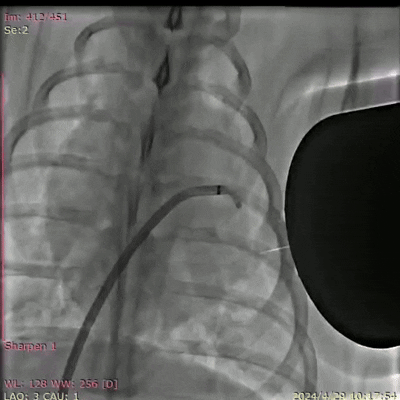

该研究首次解决了心脏左心耳血栓治疗中面临的“封堵周围漏、器械相关性血栓、心肌损伤、内皮化不完全”等核心痛点,实现在猪模型上超过10个月的稳定封堵,颠覆目前临床上使用的基于金属封堵器的封堵手段,标志着左心耳封堵技术从“固体适配”迈向“流体完全封堵”的全新阶段。

据悉,研究团队在8头巴马猪、30只SD大鼠,以及比格犬的跨物种验证中发现,该材料在实验动物介入手术中无明显出血和心率异常。3D重建显示,新型磁流体机器人能够彻底封堵左心耳,避免血栓形成,适用于各种复杂形态的左心耳。磁流体机器人在猪模型上植入2至10个月后,固化后的磁凝胶表面可形成光滑完整的心内膜,解剖学显示,无器械相关性血栓形成和心肌损伤,为团队提出的磁流体封堵术的有效性和安全性提供了有力支撑。